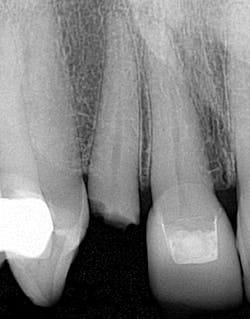

For this particular implant system (Neoss), the multi-unit analogs are not internally hexagonal, but smooth and straight; the single-unit analogs are hexagonal (figure 1). The multi-unit analogs have short screws; the single units have long screws (figure 2).

• I have prepped crowns on insufficient tooth structure and then the patient came back six months later with crown in hand (figure 3). It’s one of those moments when you realize a pin and a buildup just weren’t enough. Perhaps a post would have been helpful. I also could have told the patient that he needed to look at alternative treatment options. Now, when I am in those situations, I take a photo of the tooth, show the patient, and tell them what I can and can’t do with the tooth. Patients may not want to hear that their tooth needs to be pulled, but in the long run it’s better for everyone involved.